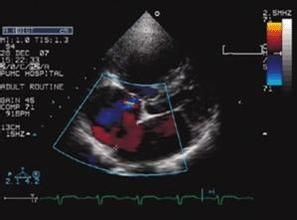

彩超作用

主要檢查心臟的形態學有沒有什麼異常,以及心功能是否正常,特別對先天性心臟病是首選的檢查方法心臟彩超是唯一能動態顯示心腔內結構、心臟的搏動和血液流動的儀器,對人體沒有任何損傷。心臟探頭就像攝像機的鏡頭,將探頭放在胸前來回移動,隨著探頭的轉動,心臟的各個結構清晰地顯示在螢幕上。